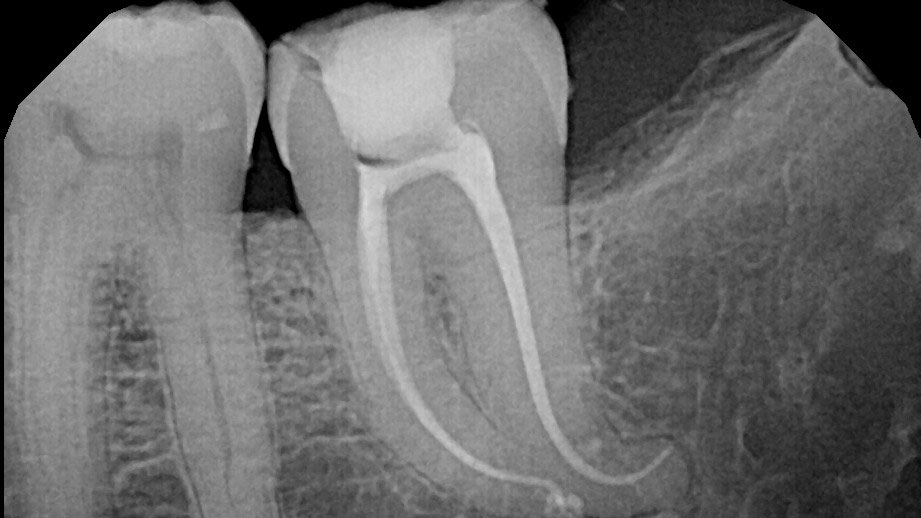

Minimally Invasive Endodontics with Laser Activated Irrigation

The primary goal in endodontics is to save teeth and preserve long-term function. If a patient presents with a diseased or inflamed pulp, it must be removed from the root canal system in a manner that preserves tooth structure and restores occlusal function.1 Over the last ten years minimally invasive endodontics (MIE) is a concept … Read more

It’s About the Agitation: The Waterlase iPlus Er,Cr:YSGG Advantage in Laser Assisted Endodontics

It has long been established in endodontics that mechanical instrumentation of the canal system is insufficient for proper disinfection. Instead, a combined chemo-mechanical approach is needed whereby mechanical and chemical interactions occur with the pulp and dentin of a tooth.1-3 Infected dentin is removed and shaped with files while irrigating solutions chemically interact with the … Read more